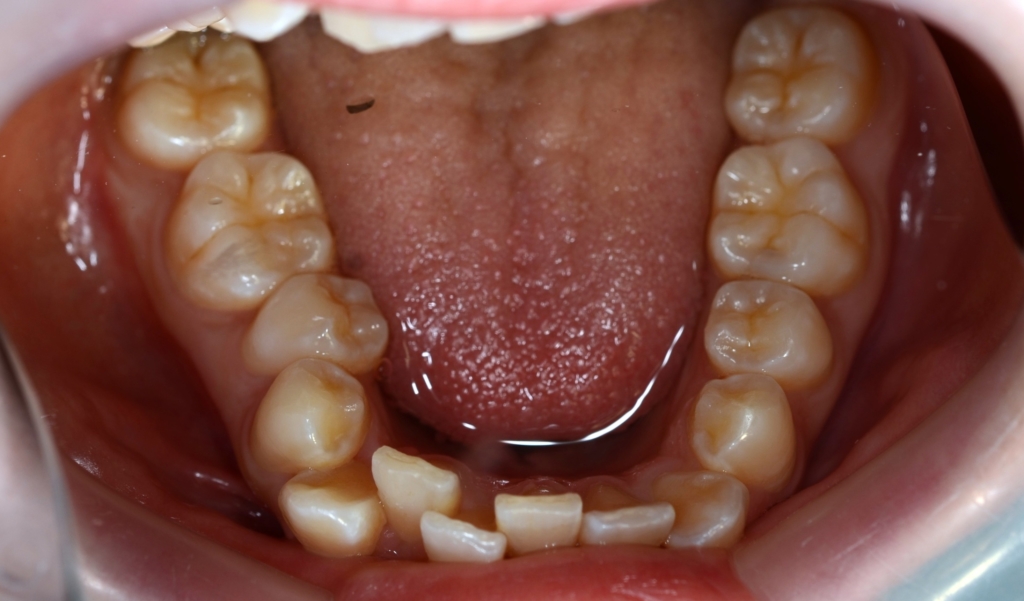

【Before】

レントゲン写真で確認すると、

この患者さんの場合、

#1.顎と歯の不調和による叢生

#2.上顎前突(出っ歯)